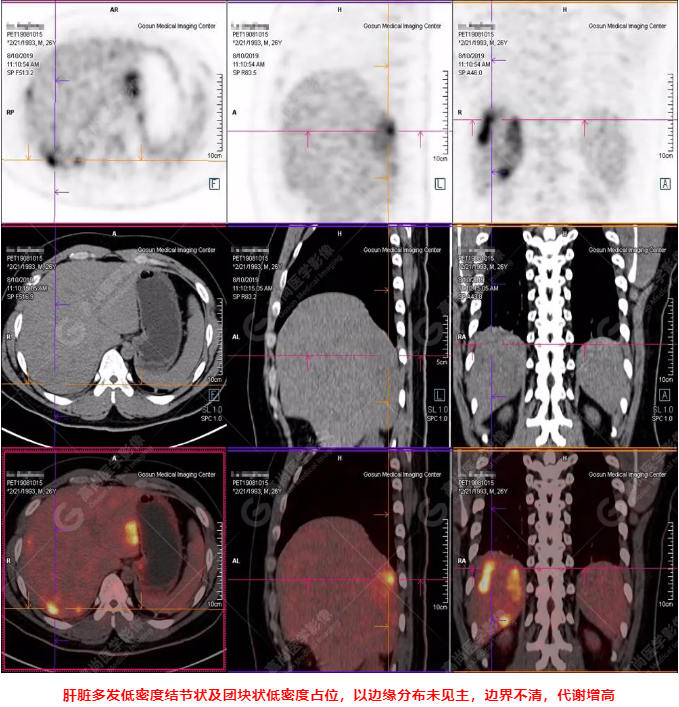

B超及CT檢查發(fā)現(xiàn):肝臟多發(fā)低密度占位。

PET/CT全身圖

PET/CT診斷

嗜酸性粒細(xì)胞增多癥肝浸潤(rùn)